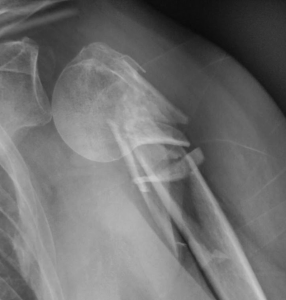

Qu’est-ce qu’une fracture de l’épaule ? L’épaule, composée de l’omoplate, de l’humérus et d’une partie de la clavicule, est une articulation complexe et susceptible de